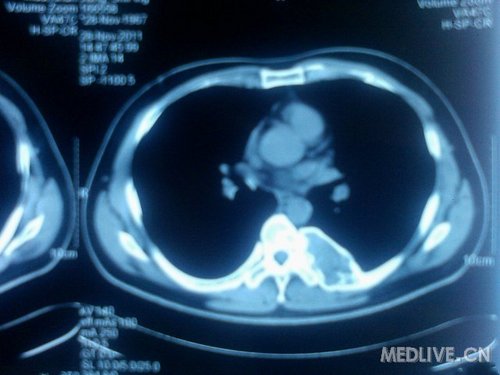

患者 男 42岁 自觉胸背部不适10个月,入院,ct见图 查体未见特殊体征,未及包快,无压痛,四肢肌力正常。血常规、凝血、肝肾功能正常,碱性磷酸酶 81(正常参考值范围)

定为在左第七肋骨处(11.28)

骨质破坏,骨转移瘤吧。

1.查ECT,估计是“多发骨转移瘤”

2.查原发病灶,消化系、泌尿系

3.查脑CT,有无脑转移。